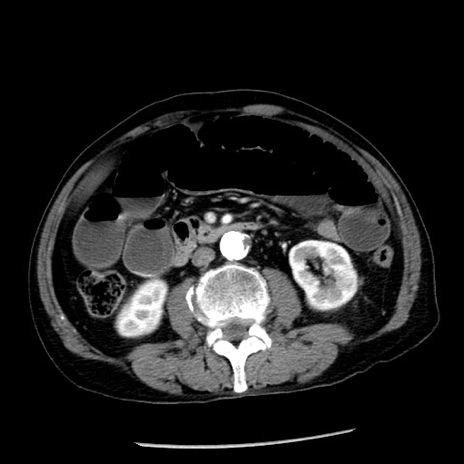

症例26(横断像)

【症例】80歳代男性

【主訴】嘔吐

【現病歴】昨晩2回嘔吐あり、今朝になっても嘔吐あり。来院。

【既往歴】胃潰瘍

【身体所見】意識清明、BT 37.6℃、BP 166/95mmHg、HR 100bpm、SpO2 97%、腹部:平坦・軟、腸蠕動音聴取良好、圧痛なし。

【データ】WBC 21900、CRP 1.46